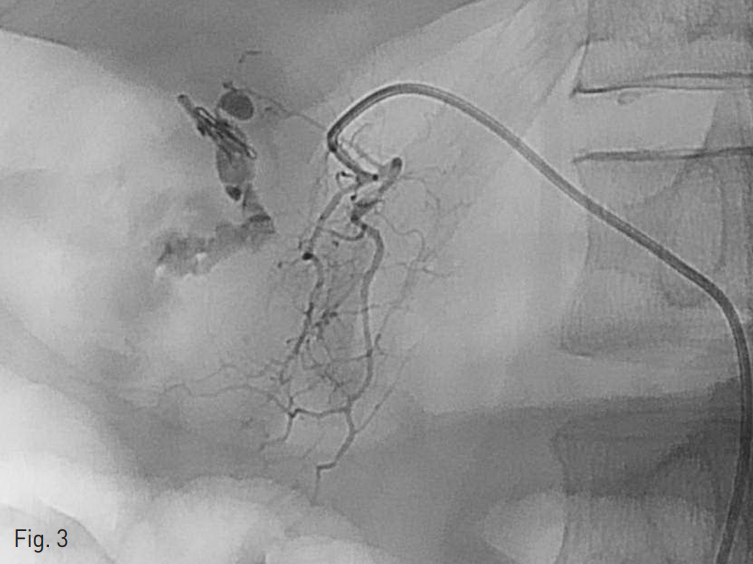

오른쪽 총대퇴동맥을 천자하여 5Fr sheath를 삽입하였다. 이후 4 Fr Yashiro catheter (Jung Sung Corp., Seoul, Korea)를 이용하여 복강동맥 (Celiac artery, Fig. 2) 과 위샘창자동맥 (Gastroduodenal artery) 혈관조영술을 시행하였으며 내시경 클립 주변으로 보이는 샘창자상부동맥 (supraduodenal artery)분지에서 가성동맥류를 동반한 혈관외 유출이 확인되었다 (Fig. 3).

Fig. 3

Gastroduodenal arteriography shows extravasation from pseudoaneurysm at the supraduodenal artery.